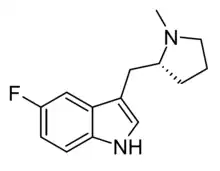

5F-MPMI[27] | (R)-5-fluoro-3-[(1-methylpyrrolidin-2-yl)methyl]-1H-indole | |

|